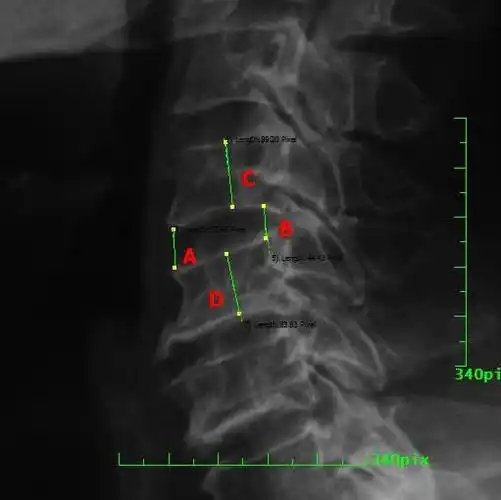

颈椎病解剖,经典影像改变,看这一篇就够了!

发现患者黄先生的头部昏沉与右手指间歇性麻木,跟颈椎错位有直接关系!

颈椎图片求解谢谢

颈椎多发小关节错位,建议摄张口位片子(观察寰枢椎)

妈妈拍的颈椎的片子,懂的瞅瞅